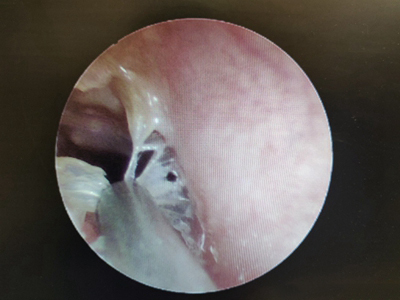

外耳道炎外耳道有白粉末里边有肉赘图

外耳道炎检查时发现外耳道内有多个白色半透明的肉赘,耳道潮湿,侧壁上还有又细又薄的白色鳞屑,患者表现为持续性疼痛,且逐渐加剧。